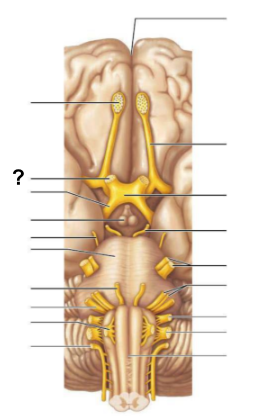

What structure, labeled “?”, is the starting point of cerebrospinal fluid circulation in the brain?

Lateral ventricle

From the lateral ventricles, CSF flows through which structure, labeled “?”, to reach the third ventricle?

Interventricular foramen

After the third ventricle, CSF flows through which narrow passage, labeled “?”, to reach the fourth ventricle?

Cerebral aqueduct

What are the two apertures, labeled “?”, through which CSF exits the fourth ventricle to enter the subarachnoid space?

The median aperture and the lateral apertures

Which structure surrounds the brain and spinal cord, allowing CSF to circulate?

Subarachnoid space

Through which structure, labeled “?”, is CSF absorbed into the venous blood?

Arachnoid villi

Into which venous system does CSF drain after passing through the arachnoid villi?

Dural venous sinuses

What is the function of the central canal in CSF circulation?